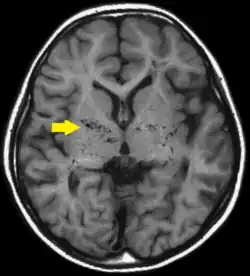

| T1-weighted MR image of moyamoya disease. Flow void in the basal ganglia is indicated by the arrow. | |

Moyamoya disease is a disease in which certain arteries in the brain are constricted. Blood flow is blocked by constriction and blood clots (thrombosis).[2] A collateral circulation develops around the blocked vessels to compensate for the blockage, but the collateral vessels are small, weak, and prone to bleeding, aneurysm, and thrombosis. On a conventional angiography, these collateral vessels have the appearance of a "puff of smoke", described as moyamoya (もやもや) in Japanese.[2]